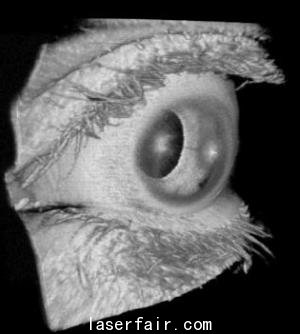

實際的例子很多,比如眼科。1.2 MHz的A-掃描速率可以在病人眨眼或者不由自主地移動眼睛之前就可以完成對視網(wǎng)膜的大范圍掃描。另一個實例就是癌癥研究,使用微型OCT探針,可以1 MHz的A-掃描速率完成兔食管、結(jié)腸和胃的成像。這意味著,該技術(shù)在使用這種可調(diào)諧VCSEL實現(xiàn)人體內(nèi)窺鏡癌癥成像的應(yīng)用領(lǐng)域取得了進(jìn)步。

Potsaid說:“已經(jīng)證實,在眼科成像中,這種VCSEL可以580 kHz的A-掃描速率、83 nm的波長調(diào)諧范圍及8.9 μm的軸向分辨率對視網(wǎng)膜進(jìn)行掃描,提供適合視網(wǎng)膜成像的成像范圍。掃描前眼需要更長的成像范圍,但是,通過降低VCSEL的掃描速率,同時保證相同的光譜掃描范圍,則可以在犧牲分辨率的情況下實現(xiàn)前眼掃描。”

在對眼睛的整個長度進(jìn)行成像方面,可以更進(jìn)一步將VCSEL的掃描速率降到50 kHz,波長調(diào)節(jié)范圍減小到45 nm。這樣做,分辨率略有下降,但成像范圍足以包括眼睛的整個長度,從眼角膜到視網(wǎng)膜。